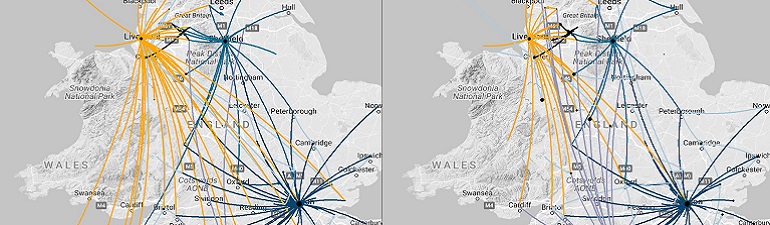

Identifying the common barriers to optimal COPD care in Japan, Canada, England, and Germany through Evidenced Care Pathways

Mapping and comparing COPD Care Pathways across 10 countries to understand barriers to optimal care: clinicians’ perspectives

Identifying the common barriers to optimal COPD care in Japan, Canada, England, and Germany through Evidenced Care Pathways

Mapping and comparing COPD Care Pathways across 10 countries to understand barriers to optimal care: clinicians’ perspectives